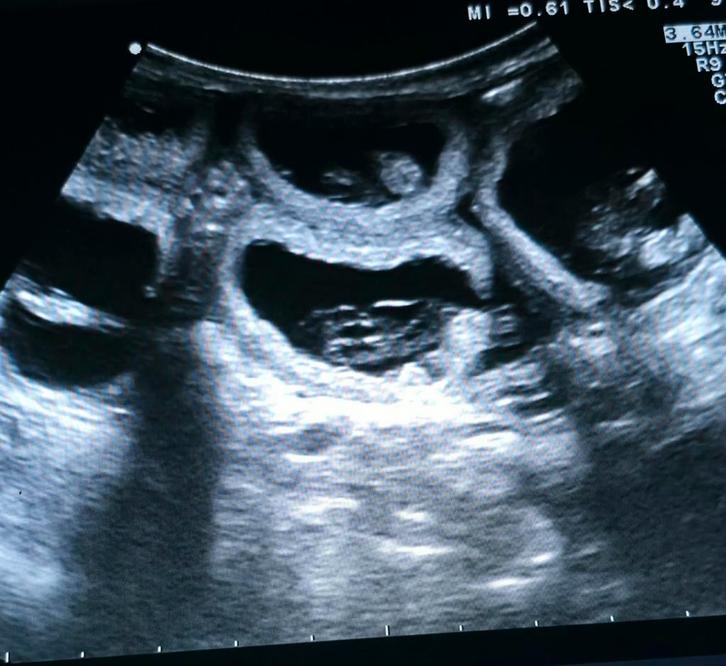

Heeft u uw teefje laten dekken en wilt u weten of de dekking geslaagd is?

Wij beschikken over een eigen professioneel echo apparaat waarbij wij kunnen kijken of uw hond drachtig is, en uiteraard jaren ervaring hiermee

Vanaf 30 dagen dracht kunnen wij het het beste zien